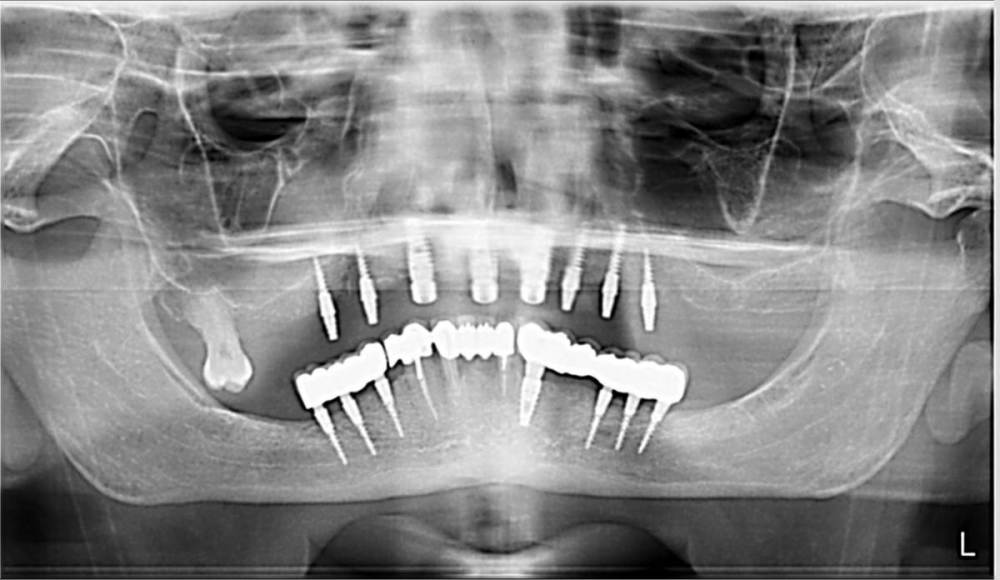

Большой Зеленый Опубликовано 5 сентября, 2023 Поделиться Опубликовано 5 сентября, 2023 Не обращайте на него внимания. Здесь имплант стоит прямо в резцовом канале. Бессимптомно 1 Ссылка на комментарий